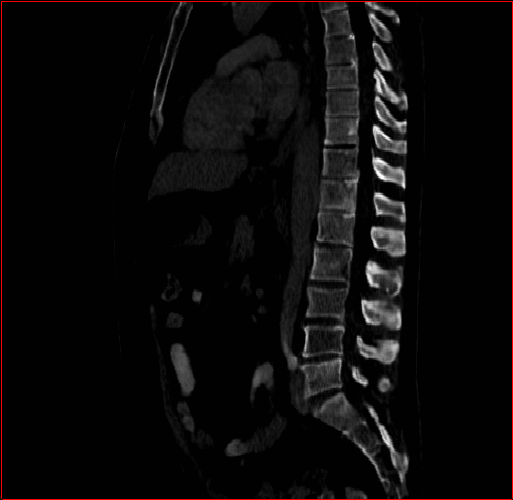

Figure 2: Qualitative comparison across axial (top row), sagittal (middle row), and coronal (bottom row) views. Columns correspond to different methods. MAISI-DDPM and MAISI-v2 in this figure are unconditional synthesis which do not use ControlNet or segmentation maps.

Qualitative Evaluation:

Figure 2 presents representative slices from the axial, sagittal, and coronal planes. GenerateCT (Hamamci et al. 2024) is a 2D model, so it lacks inter-slice consistency, leading to poor image quality in the sagittal and coronal views. MedSyn (Xu et al. 2024) produces noticeably blurry results with mosaic-like artifacts, such as region inside the red box. HA-GAN (Sun et al. 2022) generates visually sharp images but with mosaic-like artifacts, such as region inside the red box. Also, its voxel spacing is not available, which limits its applicability in real-world medical imaging tasks. Moreover, all three methods are restricted to synthesizing small anatomical regions. In contrast, both MAISI and MAISI-v2 are capable of generating high-quality 3D volumes that span larger body regions while preserving fine anatomical details and realistic structure.